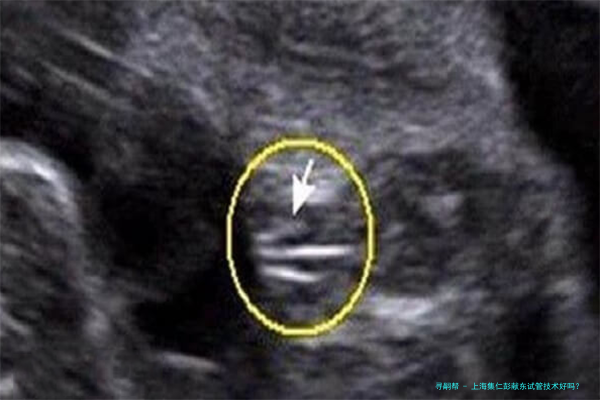

试管婴儿技术是一种人类辅助生殖技术,主要适合于因各种缘故导致的试管婴儿助孕夫妇。这个技术通过将卵子和精子在体外受精后,培育成初期胚胎,又将胚胎移植到本人体内内不断发育,一直到分娩。上海集仁遗传与不育诊疗中心的试管婴儿技术涵盖了多个方向,囊括但不仅限于: